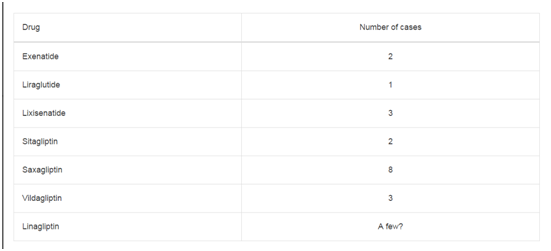

adenocarcinoma (Figure 5). Stage and myometrial invasion patterns

were compared and MELF pattern is mostly seen in stage 3, other

patterns are mostly seen in stage 1A. This comparison found to be

statistically significant (P=0,0003) (Table 1). A comparison of grade

Table 1

Table 2